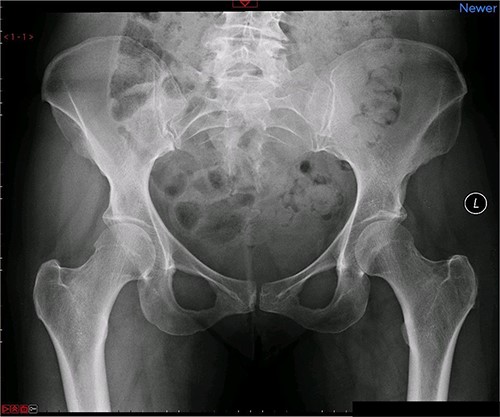

A magnetic resonance imaging (MRI) scan performed in October 2013 (Fig. 1) identified non-compressive, degenerated discs at L4/5 and L5/S1 vertebral levels. However, clinically as the patient was more tender over the left SI joint and the pubic symphysis (Fig. 2), a left sacroiliac joint fusion and symphysis pubis plating procedure was performed in August 2014 (Fig. 3). Following a short period of relief, the pain returned. Subsequently, the patient underwent a 360° fusion (front and back) of the L4/L5 and L5/S1 discs in August 2015 (Fig. 4), a year following the previous surgery. Once again, following a brief period of relief, the symptoms returned. The assumption then was that the initial fusion of the left sacroiliac joint had failed. Therefore, a revision fusion of the left sacroiliac joint and a primary fusion of the right sacroiliac joint was undertaken in August 2017 (Fig. 5).

Postoperative X-ray of the pelvis following the first fusion surgery: postoperative X-ray of the pelvis, performed in November 2014 following the first fusion surgery, showing plating of the symphysis pubis and distraction arthrodesis of the left sacroiliac joint with DIANA implant.